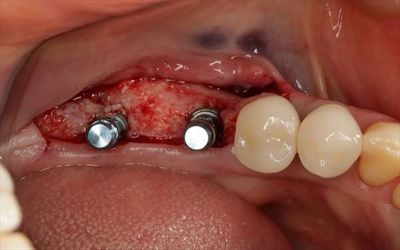

2本のインプラントを埋入しました。

ブルーのパーツは挿入ジグ=植えるためだけのパーツです。

挿入ジグを外しました。

封鎖スクリューでインプラントフィクスチャーのスクリューホールを封鎖しました。